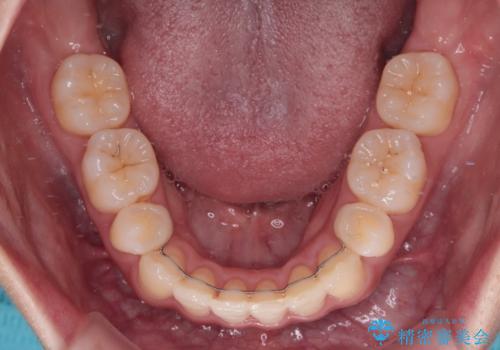

舌の突出癖を改善するためのトレーニングをしっかりと行っていただいたことで、比較的スムーズに治療を進めることができました。

口元の突出感もしっかりと改善することができました。